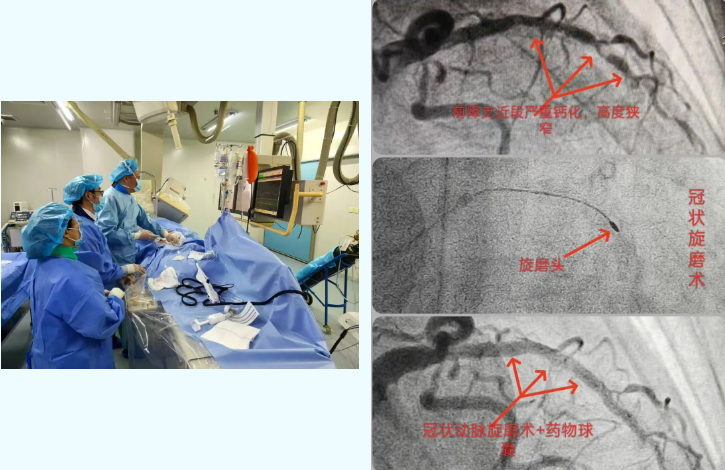

术中,医生团队经微导管指引及加强支撑,导丝通过病变后,精准置入旋磨导管,利用高速旋磨装置反复打磨坚硬钙化斑块,成功打开闭塞段血管,随后顺利实施球囊扩张及药物球囊扩张术。术后造影显示靶血管血流通畅,患者胸闷、胸痛症状即刻缓解,恢复良好,目前已顺利出院。